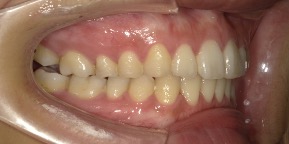

33歳女性のビフォーアフター

| 診断 | 空隙 |

| 治療方針 | 治療方針:前歯の咬合関係改善と空隙閉鎖を主な目的にて主にIPR(歯と歯の間をわずかに削合してスペースを獲得する方法)を組み込んだ動的矯正治療を行い、空隙、前歯咬合を改善後、保定を行う。臼歯部の咬合関係はプランの都合上維持することとした。 |

| 治療費 ※ | 67万8千円(診断、型取り、矯正中のメンテナンス、保定装置を含む料金) |

| 治療期間 | 6か月 |

| リスク | 1日20時間以上マウスピースを使用できない場合、歯が動かなかったり、想定しない誤差により不完全に終わる可能性がある。装着時や食事時に痛みを伴う。歯肉退縮や虫歯になるおそれがある。また、指導通りに装着できていない場合や適切なブラッシングが出来ていないとそのリスクが高くなる。歯根が短くなることがある。ごくまれに歯の神経が損傷してしまうことがある。過去にぶつけたり深い虫歯治療をしたことがあるとそのリスクはやや高くなる。矯正後には保定装置が必要。適切な使用ができない場合、後戻りの原因となる。将来的に歯並びが動いて再矯正が必要な場合がある。親知らずが正常に生えていない場合、その可能性がやや高くなる。 |